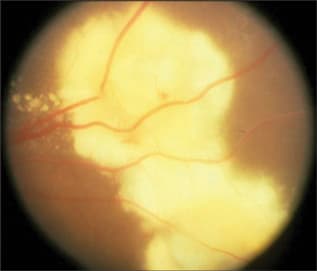

The most common presentation is posterior uveitis followed by anterior uveitis and panuveitis (Figure 6).137 Tubercular retinal vasculitis is also common and is associated with vitreous infiltrates, retinal hemorrhage, neovascularization, and neuroretinitis.138-140 Posterior involvement can be divided into 4 forms: choroidal tubercles, choroidal tuberculoma, subretinal abscess, and serpiginous-like choroiditis. The most common is multiple choroidal tubercles, which appear as small grayish nodules in the posterior pole of one or both eyes (Figure 7). These usually respond well to treatment and take up to 4 months to heal.141-143 Choroidal tuberculoma, a less common presentation in which hemorrhages and retinal folds may be seen on the tuberculoma surface,144 may be misdiagnosed as an intraocular tumor.145-147 Subretinal abscesses are yellow necrotizing granulomas that usually heal with treatment and have a good prognosis.148,149 Serpiginous-like choroiditis is a recurrent inflammation that involves the choroid and progresses to the retina, despite systemic corticosteroids and immunosuppressive agents. Additionally, the fellow eye may be affected months or years later.150,151

Figure 7. Tuberculous retinochoroiditis.